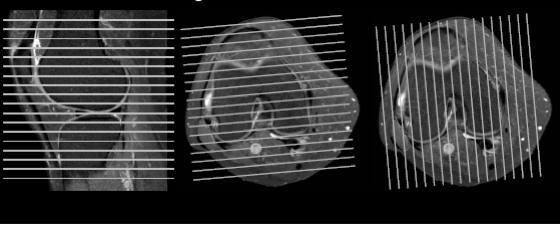

Use of Each Imaging Plane

Sagittal:

Axial:

Coronal:

Coronal Oblique ACL assessment.